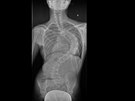

Snímek vychýlené páteře po aplikování unikátních rostoucích tyčí. Snímek skoliózy před léčbou. Martin Repko (uprostřed) je přední evropský odborník na operace zakřivení... Martin Repko (uprostřed) je přední evropský odborník na operace zakřivení... Martin Repko (uprostřed) je přední evropský odborník na operace zakřivení... Martin Repko (uprostřed) je přední evropský odborník na operace zakřivení...